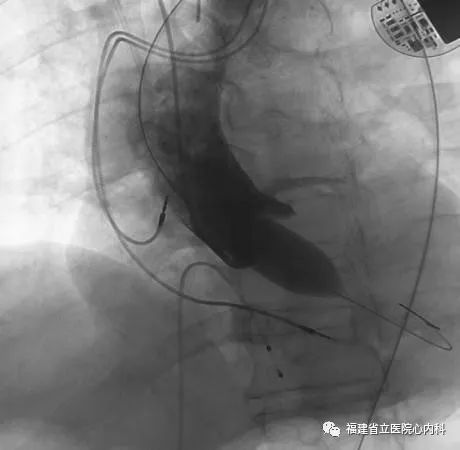

该病例主动脉瓣为功能性二叶瓣,瓣叶增厚且重度钙化,主动脉根部整体结构大需植入最大型号的人工瓣膜,患者升主动脉增宽且为横位心,增加了大瓣膜植入的难度,术者通过术前CT的精准评估,制定了对应的介入治疗策略,最终在术者稳当的控制下,Venus A- L32瓣膜精准地锚定在预期位置,术后患者症状明显改善。

瓣环

窦部

植入L32瓣膜